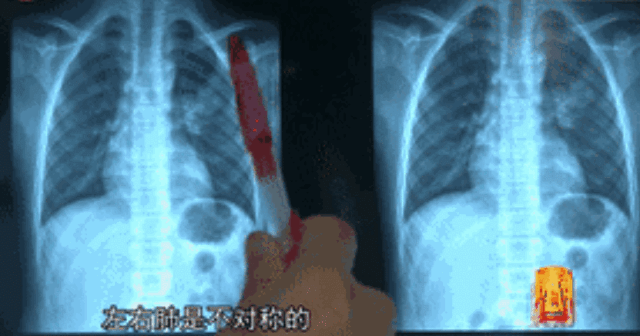

CT影像

CT检查是医学影像检查技术,一般包括平扫CT、增强CT扫描和脑池造影CT,进一步判断是否有病灶存在以及病灶的严重程度。

新冠肺炎的CT影像检测

根据病患的CT影像对比新冠肺炎胸部影像学的临床特点:早期呈现多发小斑片影及间质改变,以肺外带明显。进而发展为双肺多发磨玻璃影、浸润影,严重者可出现肺实变,胸腔积液少见。

再结合病人的临床资料(包括病人的年龄、性别、症状、体征、实验室检查、现病史、既往史、居住地、职业史等)和其他辅助检查结果(如X线检查、超声检查等),进行综合分析,得出诊断结果。